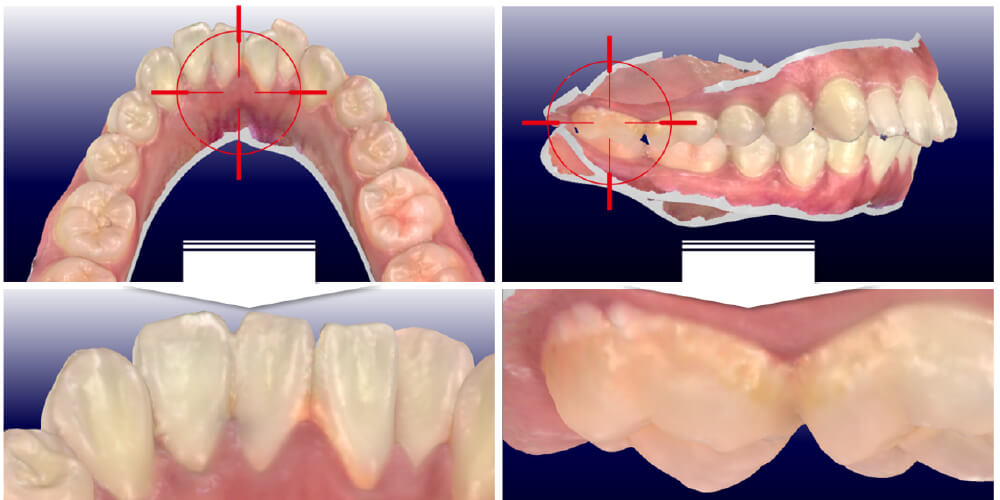

光学スキャナーの活用

高精度の光学スキャナーを用い、口腔内の「ありのままの状態」を3Dデジタル化し、歯の状態、付着したプラークや歯石を直截ご覧いただくことが治療のスタートです。特別な費用はかかりません。